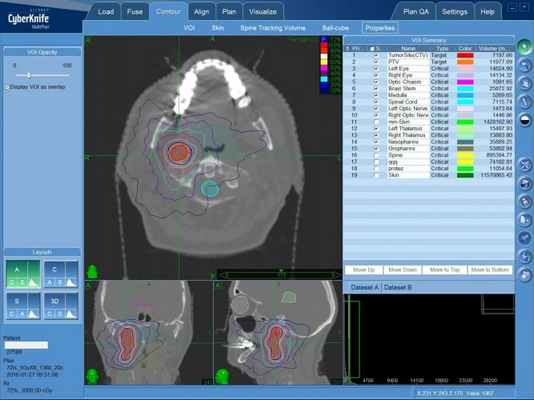

Неправильная форма опухоли, увеличивающая объем удаляемых здоровых тканей при операции, не является препятствием для КиберНожа: множественные пучки формируют зону высокой дозы излучения точно в очертаниях опухоли, не вызывая повреждения здоровых структур мозга.

Первым этапом после определения тактики лечения становится создание пространственной модели опухоли, в которой будет сосредоточена доза ионизирующего излучения, которая будет доставлена точно в опухоль. После составляется план лечения — проводится расчет количества тонких одиночных пусков излучения высокой мощности и множественных позиций, с которых они будут направлены в зону опухолевого поражения. Практическая доставка излучения в опухоль будет проведена из различных положений мобильного линейного ускорителя, размещенного на роботизированном манипуляторе.

Безоперационное лечение параганглиомы на КиберНоже — план лечения